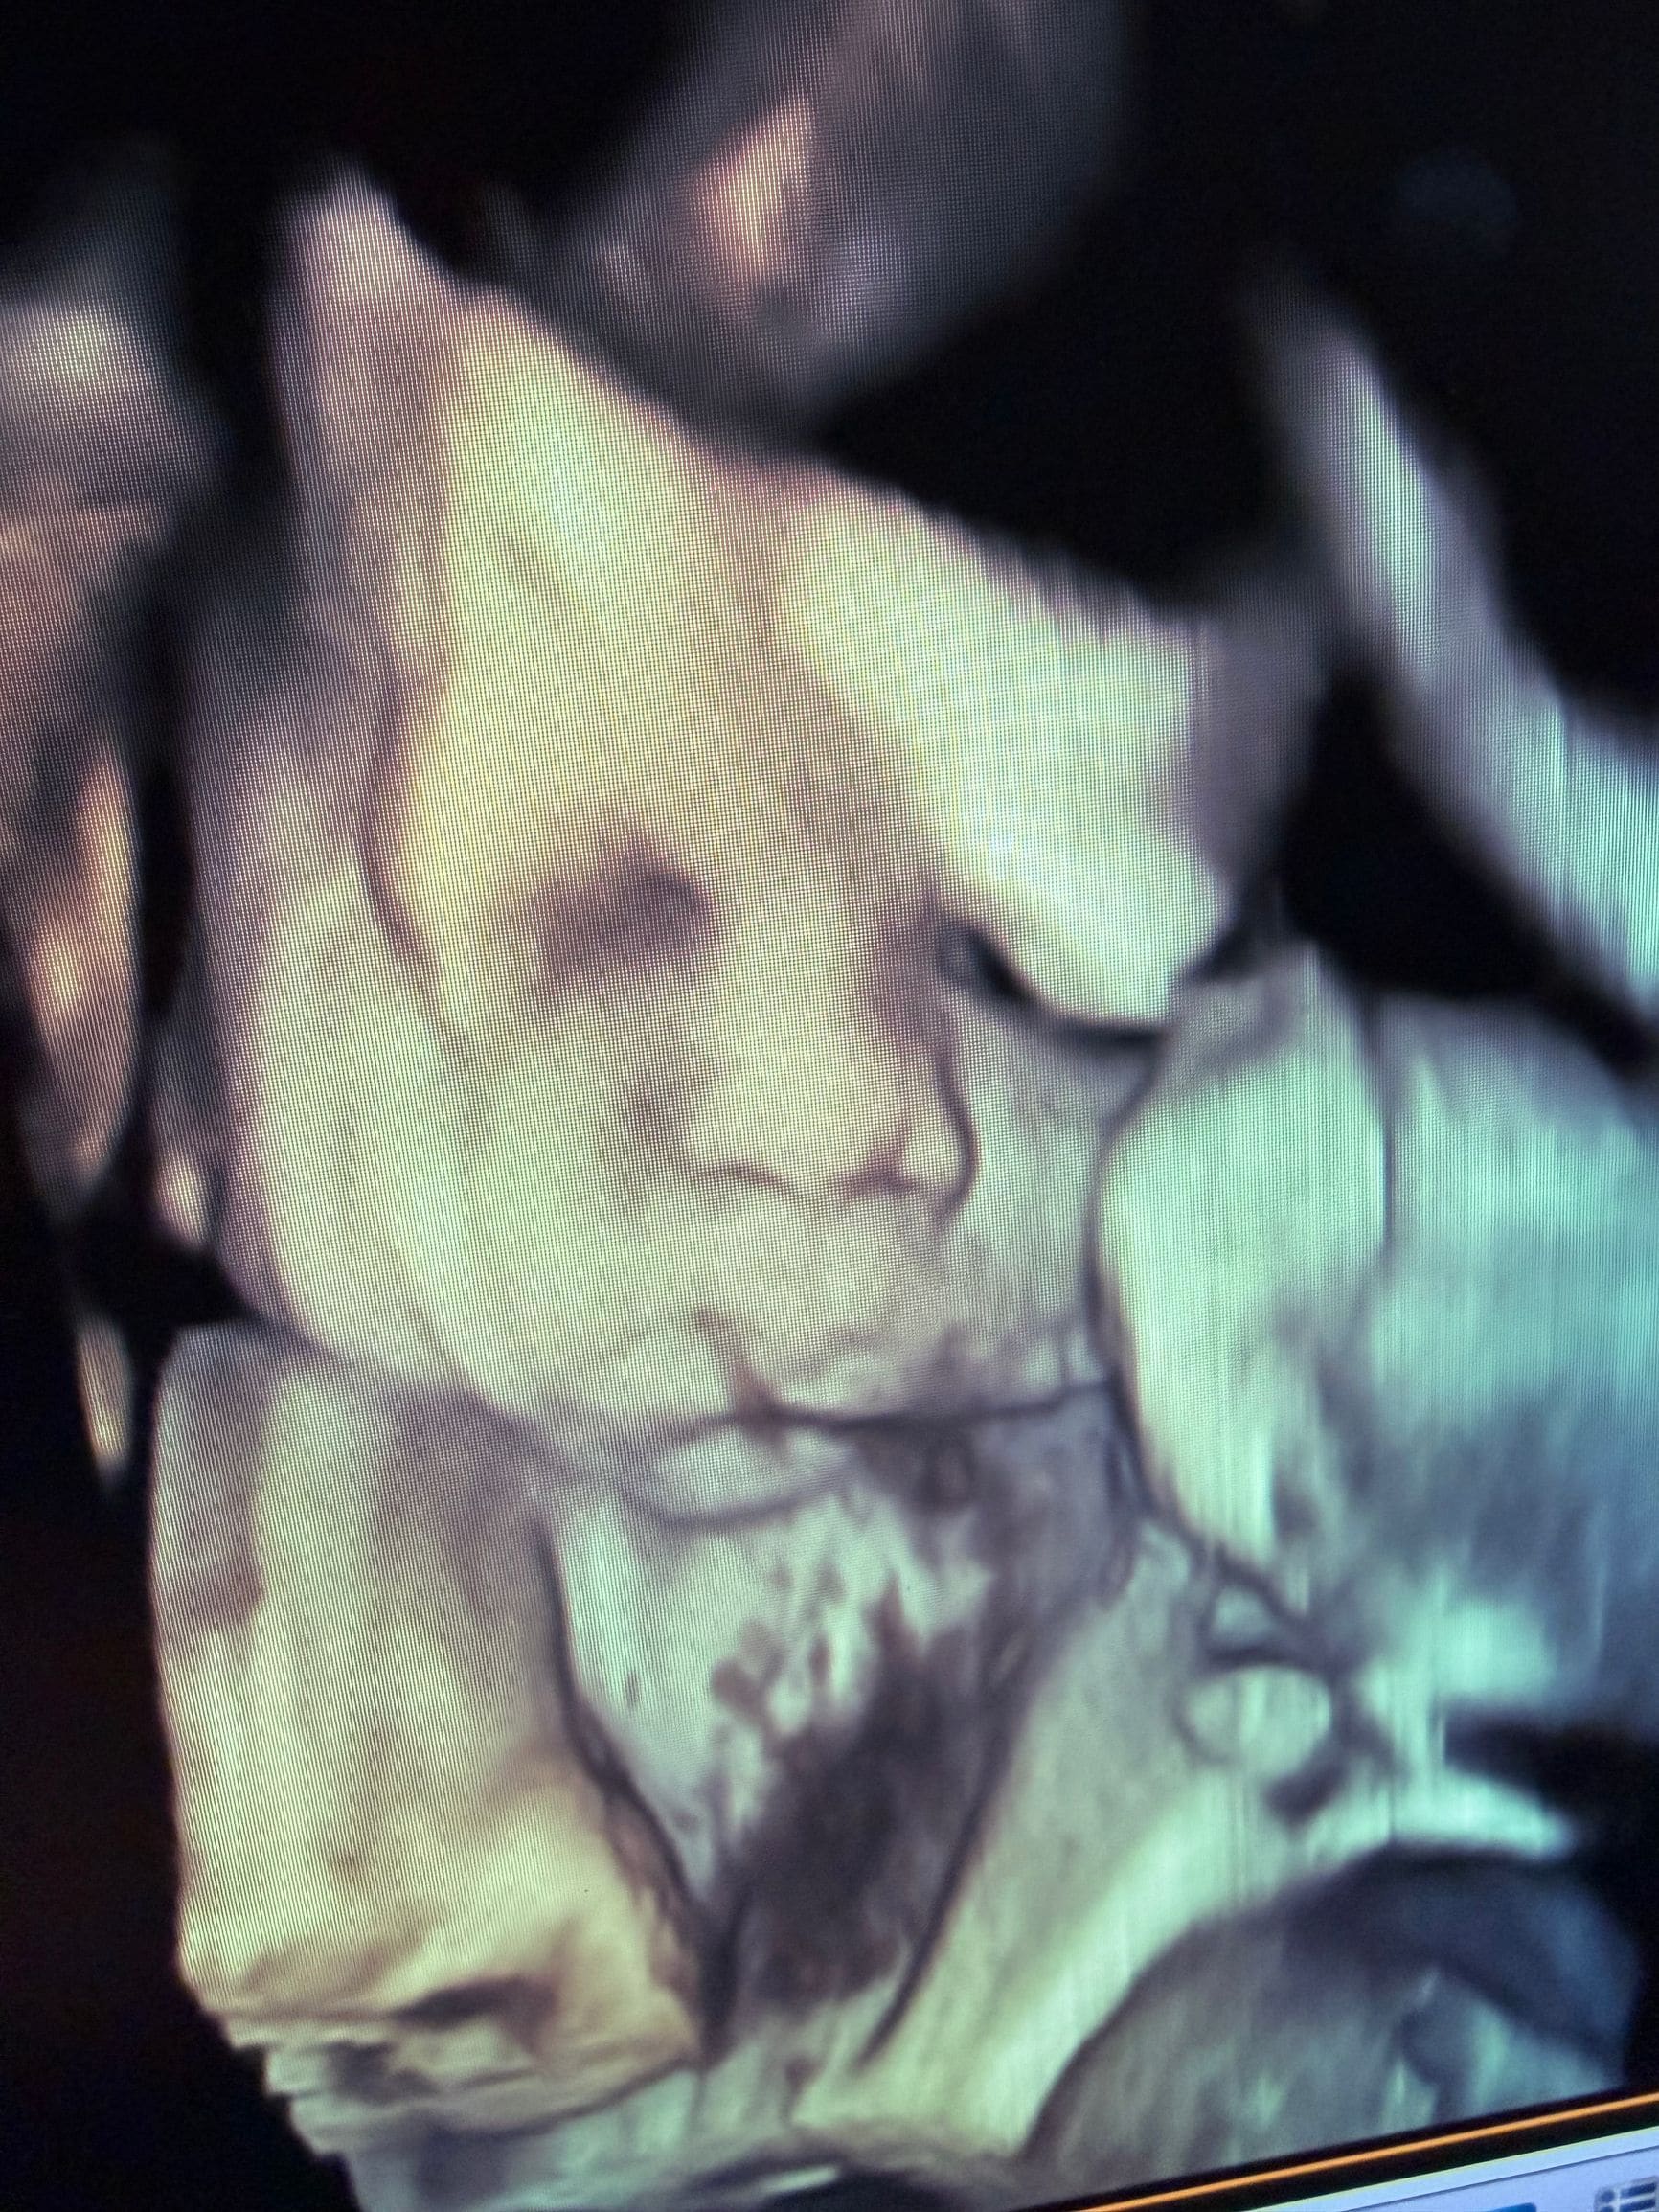

4D Ultrasound